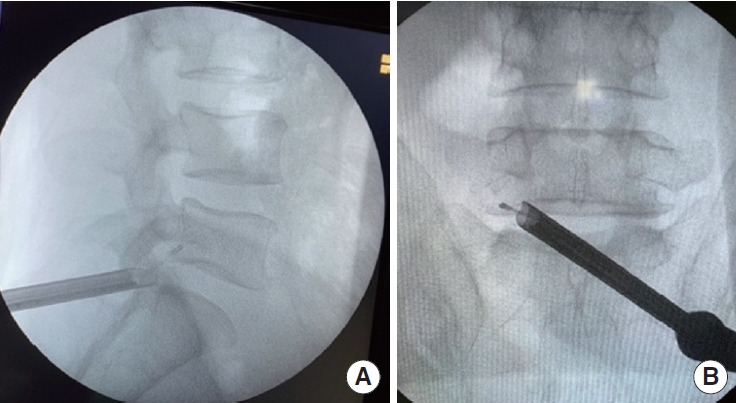

目的:描述全内窥镜腰椎间孔成形术与中线皮肤切口(FEFM)和外侧隐窝减压手术,并报告其1年随访的临床结果。方法:对连续行FEFM手术的腰椎椎间孔和/或外侧隐窝狭窄患者进行回顾性分析。采用视觉模拟量表(VAS)评估术后1年的背部和腿部疼痛以及Oswestry残疾指数(ODI)。并记录并发症及复发率。结果:共纳入51个级别30例(L3-4, 6例[11.8%];L4-5, 23 [45.1%];L5-S1 22例[43.1%])。术前、术后第1天、第3个月、第6个月、第1年VAS评分分别为9.16、1.7、1.36、1.3、1.43。术前、术后3个月、6个月和1年的ODI评分分别为46.63、11.5、10.66和10.46(结论:FEFM是治疗椎间孔和/或外侧隐窝狭窄的有效方法。它显示了通过单一入路点减压双侧椎间孔和外侧隐窝狭窄的能力。

Objective: To describe the full-endoscopic lumbar foraminoplasty with midline skin incision (FEFM) and lateral recess decompression procedure and to report its clinical outcomes at the 1-year follow-up.

Conclusion: FEFM is an effective procedure for treating foraminal and/or lateral recess stenosis. It demonstrates the capability to decompress both bilateral foraminal and lateral recess stenosis through a single-entry point.